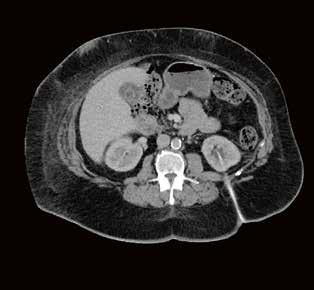

Fall 1:

Biphasische Abdomen-CT bei einer deutlich adipösen Patientin. Hier lässt sich sowohl Dosis sparen als auch die Qualität der Rekonstruktionen verbessern. Beispielsweise findet sich deutlich weniger Bildrauschen, insbesondere im Bereich der parenchymatösen

Portalvenöse Abdomen-CT. Auch hier ist die Dosis am Aquilion Prime SP mit AiCE geringer, zudem auch hier geringeres Bildrauschen mit sehr guter Abgrenzbarkeit, beispielsweise von Leberläsionen.

Abb. 1 a: biphasische Abdomen-CT, Canon Aquilion Prime, Rekonstruktion: AIDR 3D; DLP 1003,6 mGy × cm / 18,1 mSv. Abb. 2 a: biphasische Abdomen-CT, Canon Aquilion Prime, Rekonstruktion: AIDR 3D; DLP 1003,6 mGy × cm / 18,1 mSv. Abb. 1 b: biphasische Abdomen-CT, Canon Aquilion Prime, Rekonstruktion: AiCE; DLP 716,5 mGy × cm / 12,9 mSv. Abb. 2 b: biphasische Abdomen-CT, Canon Aquilion Prime, Rekonstruktion: AiCE; DLP 716,5 mGy × cm / 12,9 mSv. Oberbauchorgane.